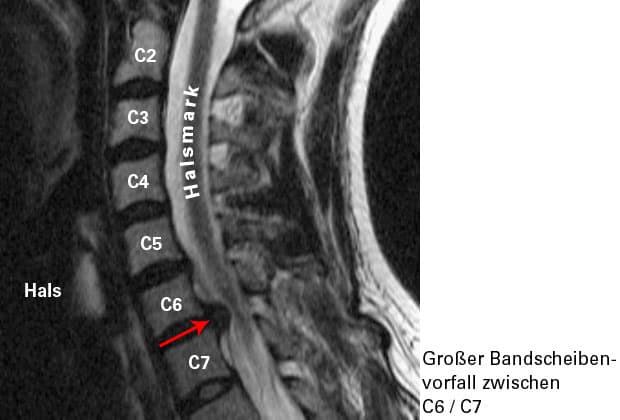

1. BSV an der HWS

Je intensiver der Schmerz und je präziser die Schmerzstraße, desto wahrscheinlicher ist ein BSV im Bereich der HWS als Ursache anzunehmen. Schmerzen der HWS selbst müssen nicht zwingend gleichzeitig bestehen. Bestimmte HWS-Bewegungen können den Arm-Schmerz verstärken. Die Ausprägung der Beschwerden hängt davon ab, wie stark der BSV die betroffene Nervenwurzel reizt bzw. komprimiert. Bei Lähmungen von Muskeln kann bereits durch die körperliche Untersuchung ein BSV als gesichert angenommen werden.